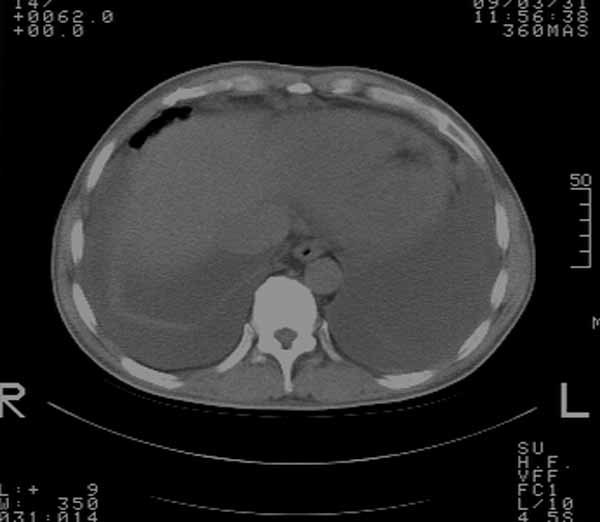

以下是引用余辉在2009-3-31 18:43:00的发言:[br]肺水肿,双侧心腔积液,心包积液,心影增大,疑似心衰

以下是引用wangyong1977在2009-3-31 20:46:00的发言:[br]肺水肿,双侧胸腔积液,心包积液,心影增大,疑似心衰 [br]

以下是引用宇宙ct在2009-3-31 18:57:00的发言:[br]肺水肿,双侧心腔积液,心包积液,心影增大,疑似心衰 [br] [br]